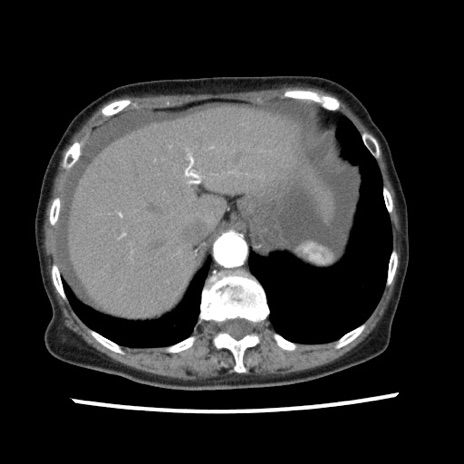

症例1(横断像)

【症例】80歳代女性

【主訴】腹痛

【現病歴】8時間前から腹痛あり来院。

【既往歴】糖尿病、脂質異常症、子宮体癌にて子宮全摘術

【身体所見】意識清明・会話良好だが腹痛で苦悶様、全腹部にわたって反跳痛と圧痛あり

【データ】WBC 13600、CRP 0.14、LDH 224、CK 90